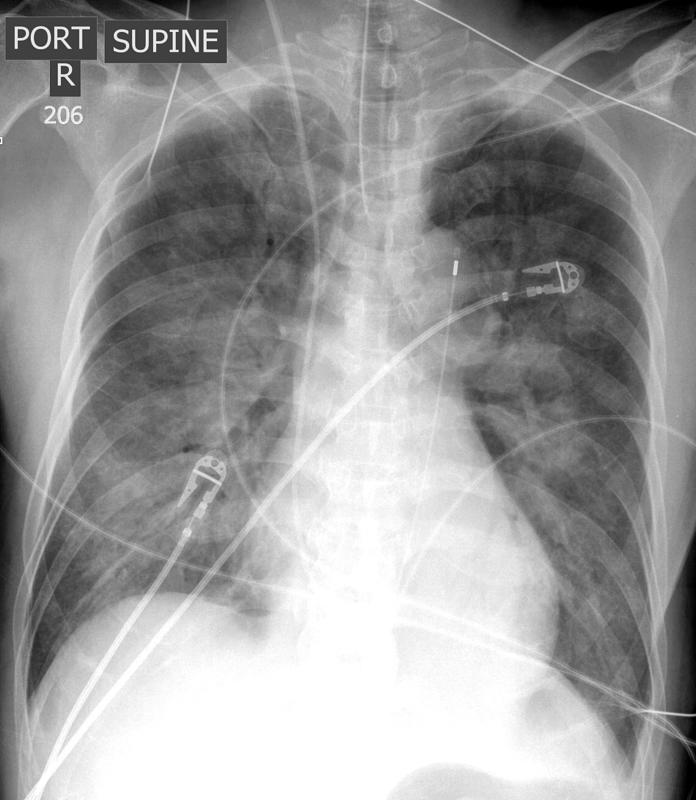

APE IABP